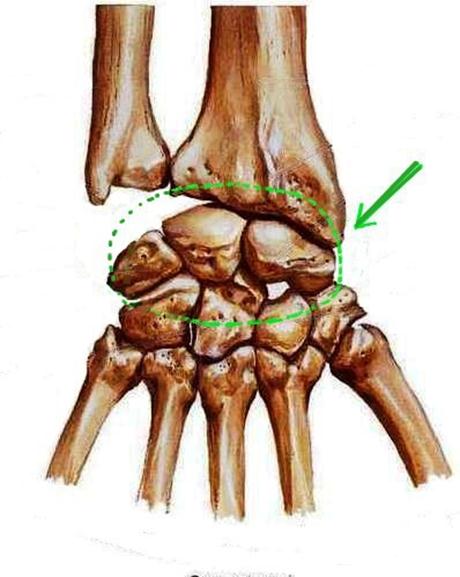

S: Числом 10 обозначена os ### (латинский язык).

S: Цифра 5 обозначает ossa ### (латинский язык).

S: Цифрой 8 обозначена os...

S: Числом 12 обозначена os...

S: Числом 13 обозначена os...

S: Цифра 3 указывает на...

S: Цифра 2 указывает на …

S: Цифра 1 указывает на....